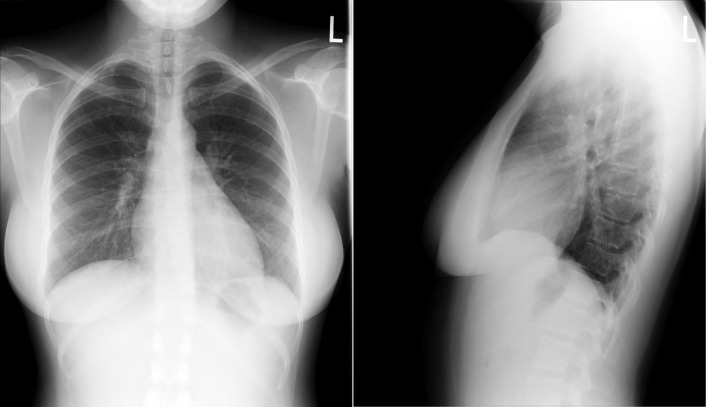

A patent foramen ovale is present in 25% to 30% of the adult population ( Figs. 18-1 to 18-4 ). Any magnitude of shunting across it in normal circumstances is undetectable radiographically. Percutaneous patent foramen ovale closure devices are fairly commonly inserted and are radiographically evident.